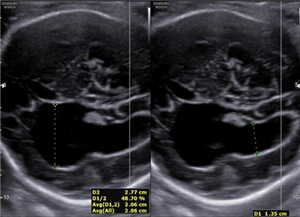

Thai ngoài tử cung ở buồng trứng